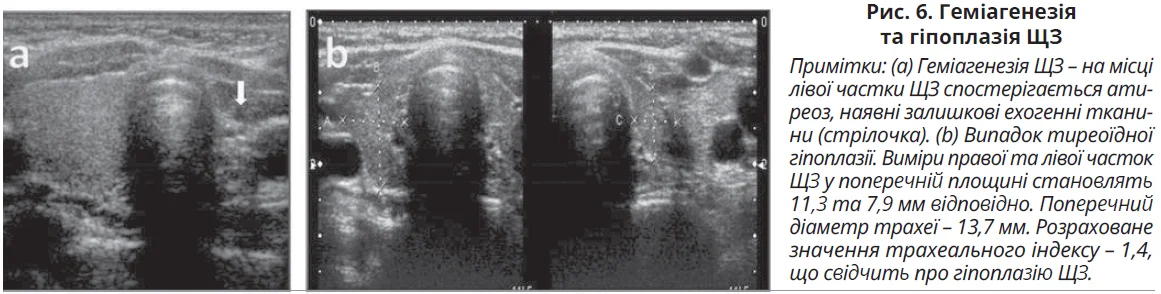

Атиреоз і залишкові ехогенні тканини в ложі ЩЗ, що є двобічними при агенезії, при геміагенезії є однобічними. Геміагенезія ЩЗ може бути випадковою знахідкою в безсимптомних еутиреоїдних пацієнтів, а в дітей ця аномалія може проявлятися зниженням рівнів тиреоїдних гормонів у підлітковому віці, коли потреба в них є високою. На УЗД-знімках може спостерігатися однобічна відсутність частки ЩЗ і наявність нормальної або збільшеної частки на протилежному боці.

Гіпоплазія ЩЗ є причиною 5% випадків уродженого гіпотиреозу. На УЗД-знімках залоза зазвичай гіпоехогенна, ортотопічна, нормальної форми та нормального розміру або зменшена для свого віку. Гіпоплазію можна діагностувати в новонароджених із трахеальним індексом <1,7 і низьким поглинанням на сцинтиграфії. Геміагенезія та гіпоплазія ЩЗ показані на рисунку 6.